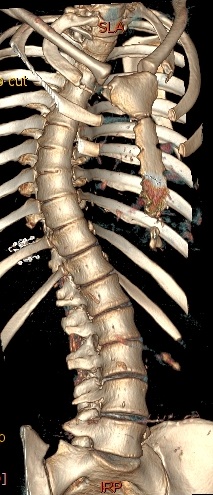

Рис - КТ Сколиоз

На этапе планирования обязательно выполняют (постуральные) рентгенограммы в двух проекциях (сбоку и спереди), при котором снимок захватывает весь позвоночник. Также необходимы (функциональные) снимки с наклонами в сторону. Если на таких снимках позвоночный столб плохо выравнивается, то деформацию считают ригидной.

Рис - Сколиоз